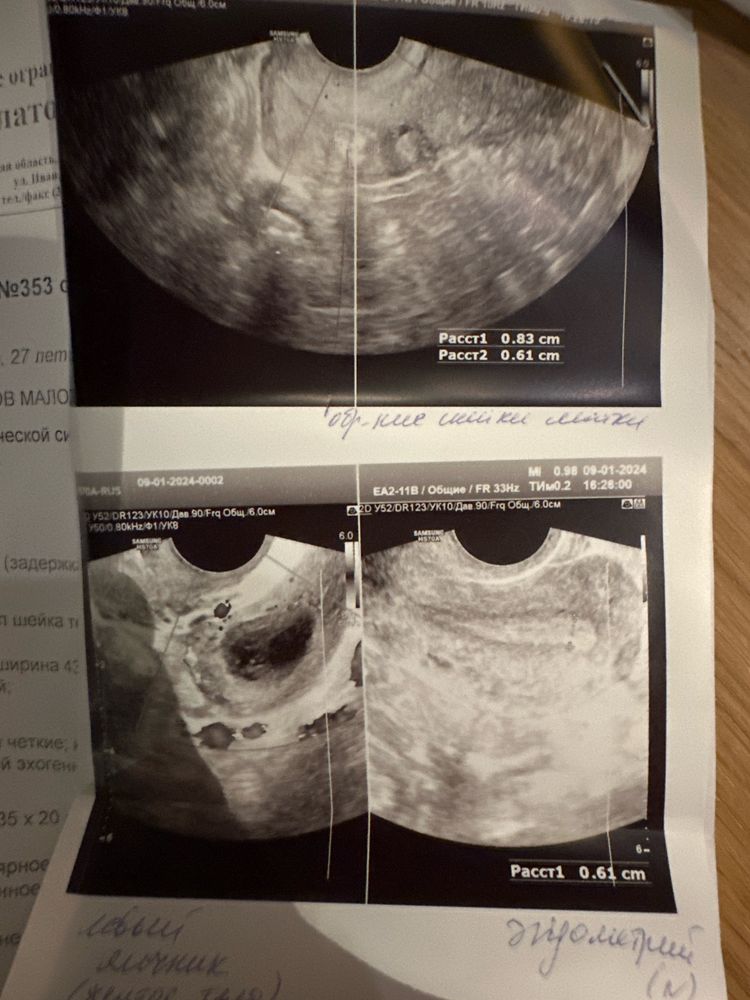

Делала узи 9.01.24 5 день задержки, тест отрицательный. Овуляция была как сказал врач дней 4-6 назад примерно. В левом яичнике желтое тело . Менструация не наблюдается, мол по узи видно что не вот скоро начнется .

Так по узи матка чистая , но хотелось бы верить что беременность наступила , просто на узи и на тесте еще не показывает . Сегодня уже 6 день задержки ( на 4 день задержки была мазня чуть чуть совсем ) пока не предвещается месячных.